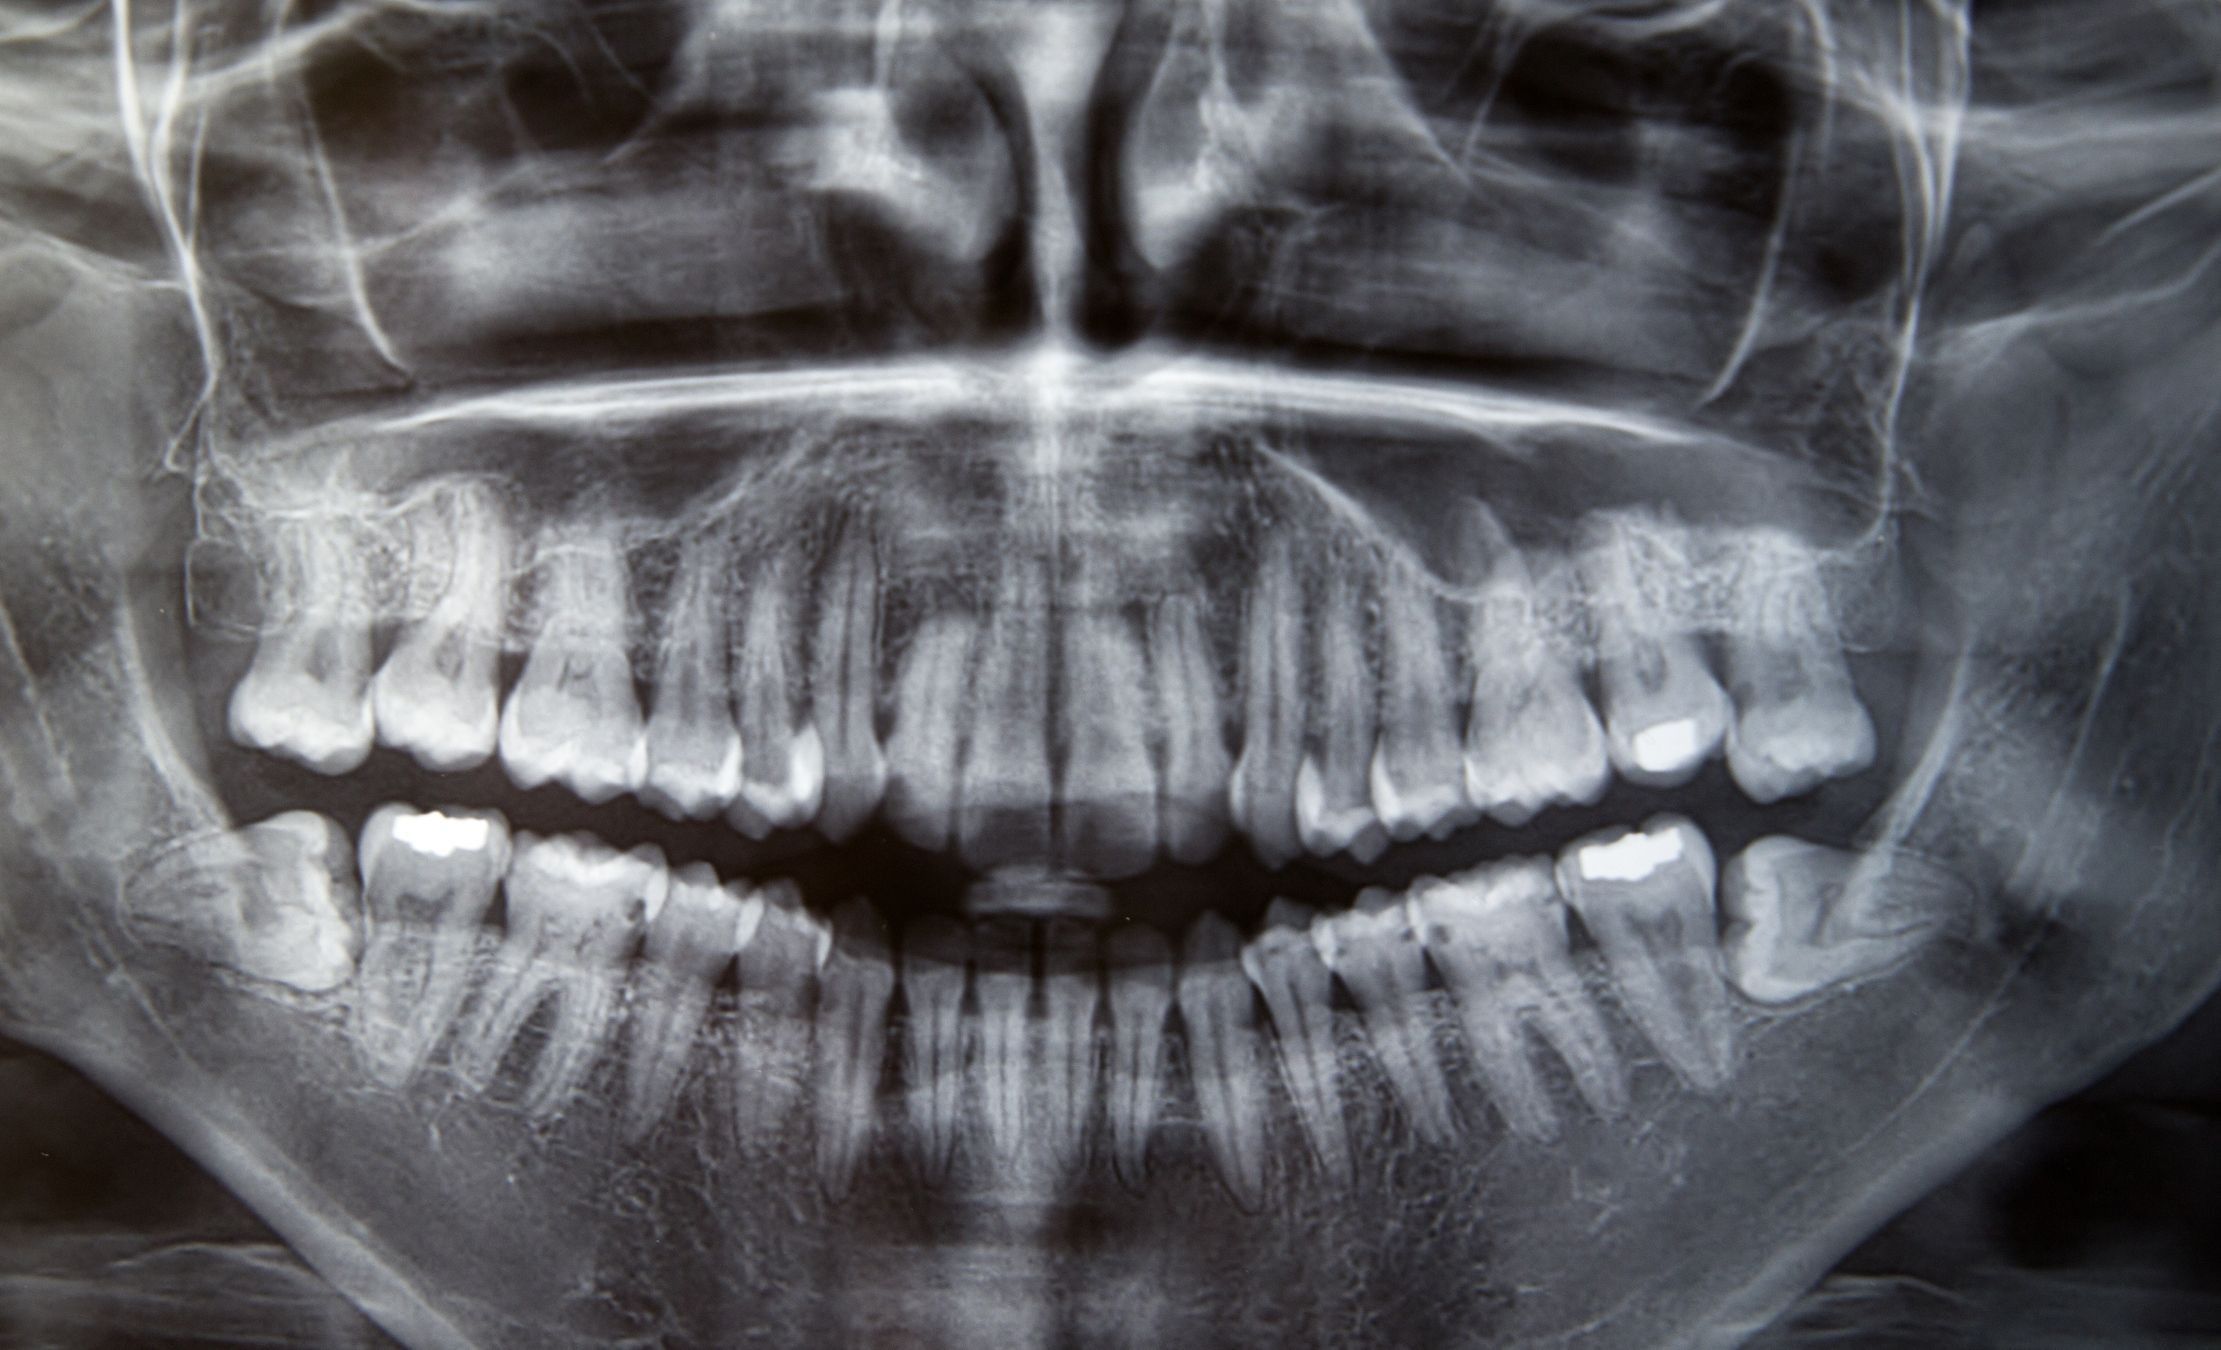

El hueso alveolar es como conocemos a la estructura ósea sobre la que se integran las raíces dentales. Junto con los tejidos gingivales mantienen a la pieza dental en su